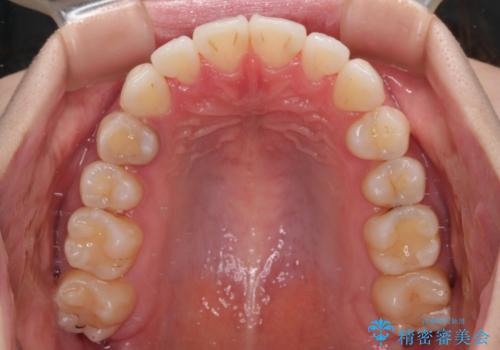

- 上下前歯の隙間を気にして来院された患者様です。

前歯が、舌の突出癖により上下前歯が非接触となっている状態でした。

上下前歯が非接触である開咬は、インビザラインによる治療がお勧めではありますが、しっかりと使う自信がないとのことで、ワイヤー装置にて治療を行うこととしました。